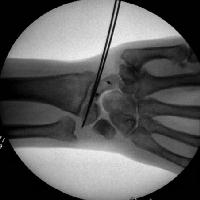

Intraoperative correction of scapholunate rotation using K-wires as joysticks on each bone.

Click for larger image

Scapholunate pins and bone anchors - intraoperative fluoroscopy.